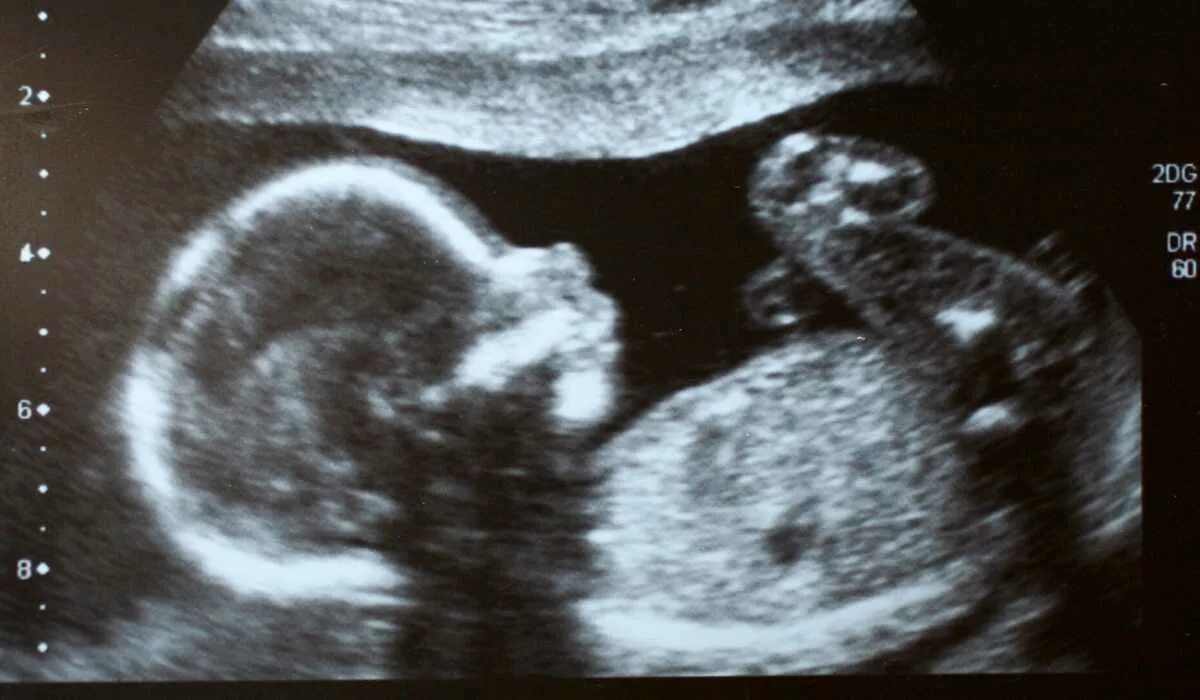

Скрининг 21 неделя